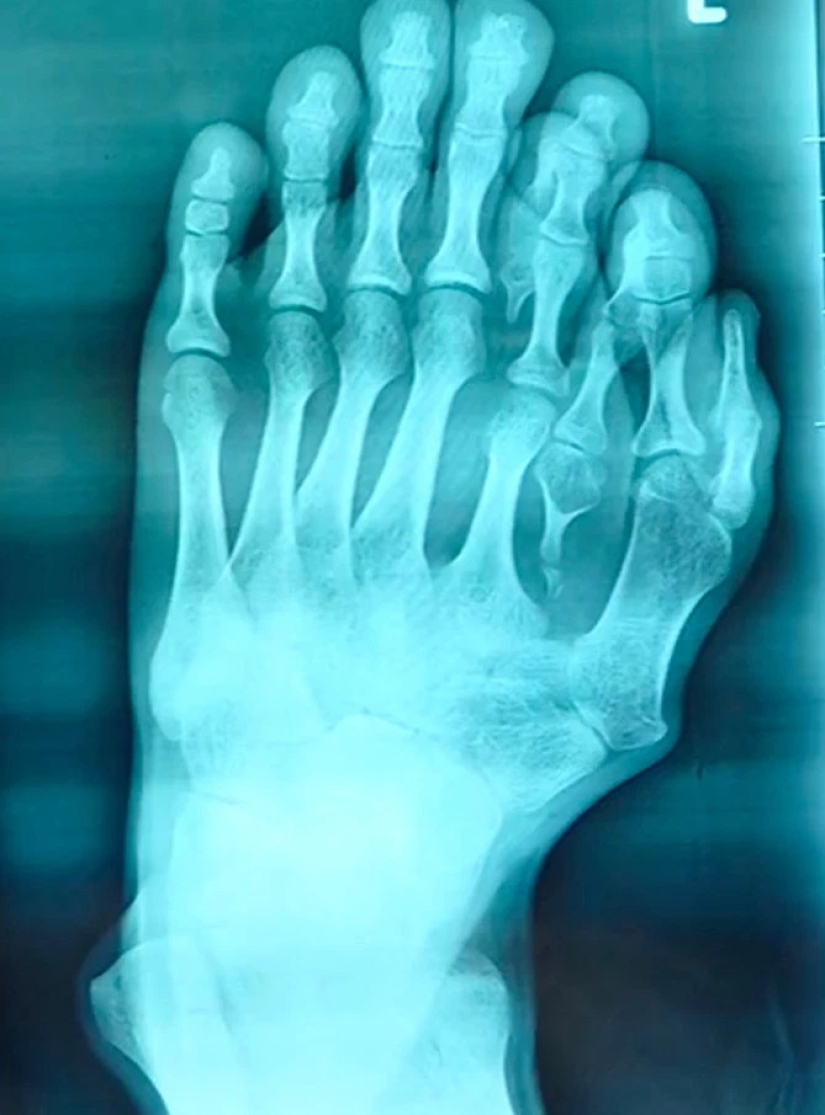

Por Pictolic https://mail.pictolic.com/es/article/la-felicidad-nunca-es-demasiado-los-chinos-han-vivido-mucho-tiempo-con-14-de-los-dedos-de-los-pies-teniendo-en-cuenta-la-anomala-de-feliz-signo.htmlEl hombre que nació con cuatro dedos adicionales en la pierna izquierda, y el pensamiento acerca de la cirugía para deshacerse de ellos, porque sus padres creían que esta anomalía signo de buena suerte. Sólo recientemente, de 21 años, hombre Chino fue operado, dando la posibilidad de usar zapatos y encontrar la felicidad en su vida personal. Averiguar cómo el chico vivía con un poco de desviación de nuestro artículo.

Los padres de 21 años, China por el nombre de Azzun cree que cuatro dedos adicionales en mi pie izquierdo, el hijo, es un signo de buena fortuna. Los jóvenes anomalía trajo un montón de molestias en la vida cotidiana, así como el sufrimiento físico: en diez años se dejaron de usar sandalias porque el sangrado de las heridas en sus piernas.

Cuando Azzouni madurado, se convirtió para el asesoramiento a los cirujanos en el hospital Quirúrgico de Shunde Heping Hospital de Foshan ciudad. Su médico Xiang (Xiang Wu), dijo que estas operaciones están haciendo en la infancia, por lo que el jugador de 21 años de edad paciente era un caso especial.

El doctor dice que los niños que nacen con discapacidades necesitan para operar hasta seis años antes de ir a la escuela. Esto es importante para el estado psicológico del niño, y para acelerar el proceso de recuperación y adaptación.El joven cree que su vida va a conseguir, finalmente, mejor. Él espera encontrar a una chica que va a ser feliz. El chico está muy agradecido a los cirujanos para darle la oportunidad de ser normal. La superstición de los padres casi destruyó la vida de Assuna, pero el sentido común prevaleció, y ahora el chico tiene una oportunidad para un futuro mejor.

Azzouni no es el único Chino con dedos adicionales. Tres meses bebé llamado JonJon — el propietario, de 15 de dedos y 16 de los dedos de los pies. Además, sus dos manos en cada mano, pero no los pulgares.